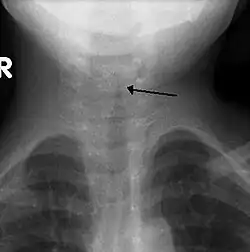

| The steeple sign as seen on an AP neck X-ray of a child with croup | |

A frontal X-ray of the neck is not routinely performed,[4] but if it is done, it may show a characteristic narrowing of the trachea, called the steeple sign, because of the subglottic stenosis, which resembles a steeple in shape. The steeple sign is suggestive of the diagnosis, but is absent in half of cases.[12]